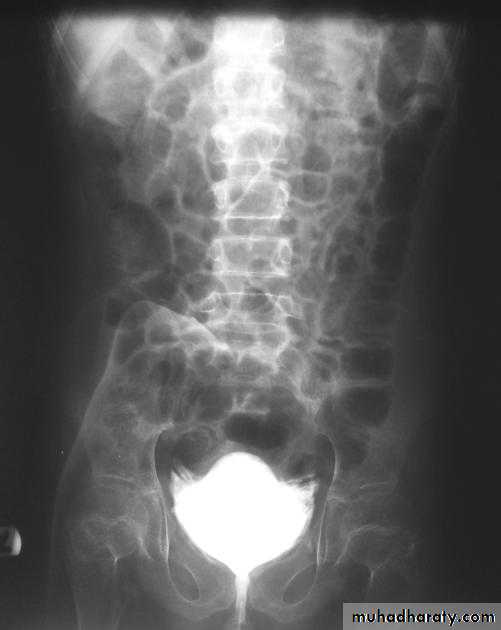

Infestation With Schistosoma haematobium. Plain radiograph demonstrates calcification in the wall of the bladder (open arrows) and in the wall of the left ureter (curved arrow). The bladder is filled with urine